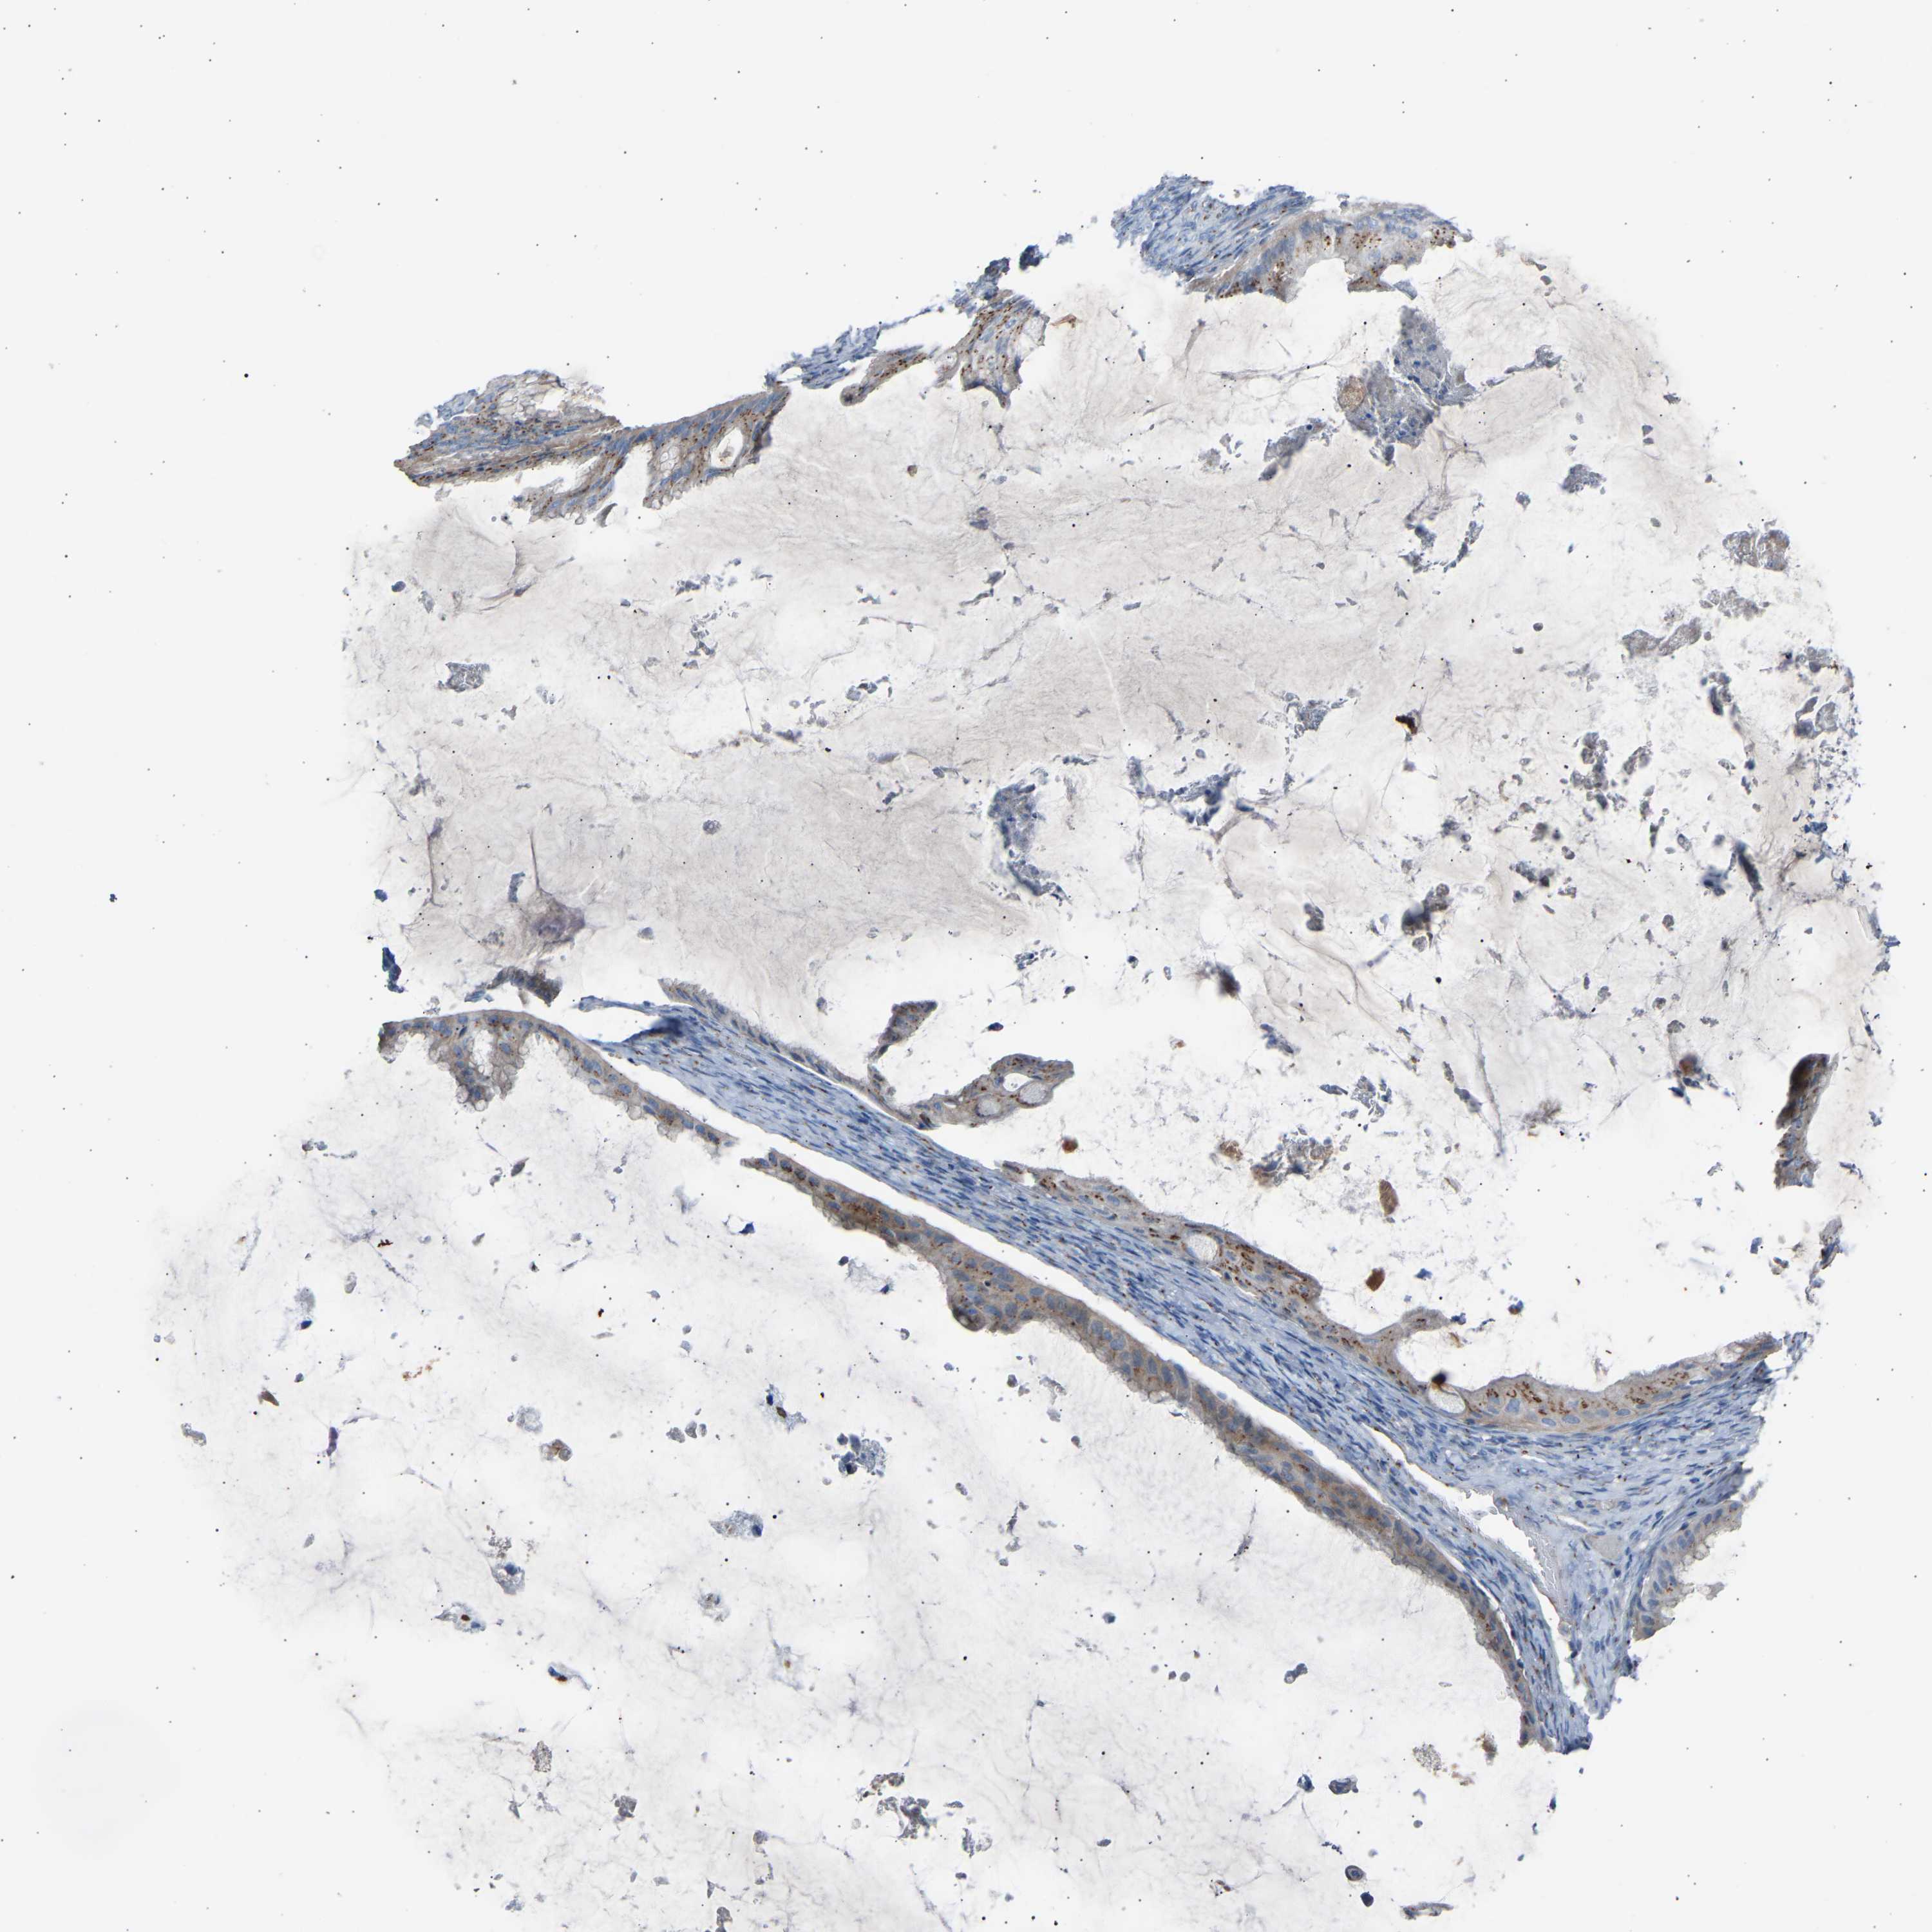

OVARIAN CANCER - Protein expressioni

A mouse-over function shows sample information and annotation data. Click on an image to view it in a full screen mode. Samples can be filtered based on level of antibody staining by selecting one or several of the following categories: high, medium, low and not detected. The assay and annotation is described here.

Note that samples used for immunohistochemistry by the Human Protein Atlas do not correspond to samples in the TCGA dataset.

Antibody stainingi

Antibody staining in the annotated cell types in the current human tissue is reported as not detected, low, medium, or high, based on conventional immunohistochemistry profiling in selected tissues. This score is based on the combination of the staining intensity and fraction of stained cells.

Each image is clickable and will lead to virtual microscopy that enables deeper exploration of all samples and also displays staining intensity scores, fraction scores and subcellular localization as well as patient and tissue information for each sample.

Antibody HPA020060

Staining

High

Medium

Low

Not detected

Intensity

Strong

Moderate

Weak

Negative

Quantity

>75%

75%-25%

<25%

None

Location

Nuclear

Cytoplasmic/membranous

Cytoplasmic/membranous,nuclear

Cystadenocarcinoma, serous, NOS

Carcinoma, endometroid

Cystadenocarcinoma, mucinous, NOS

Carcinoma, NOS